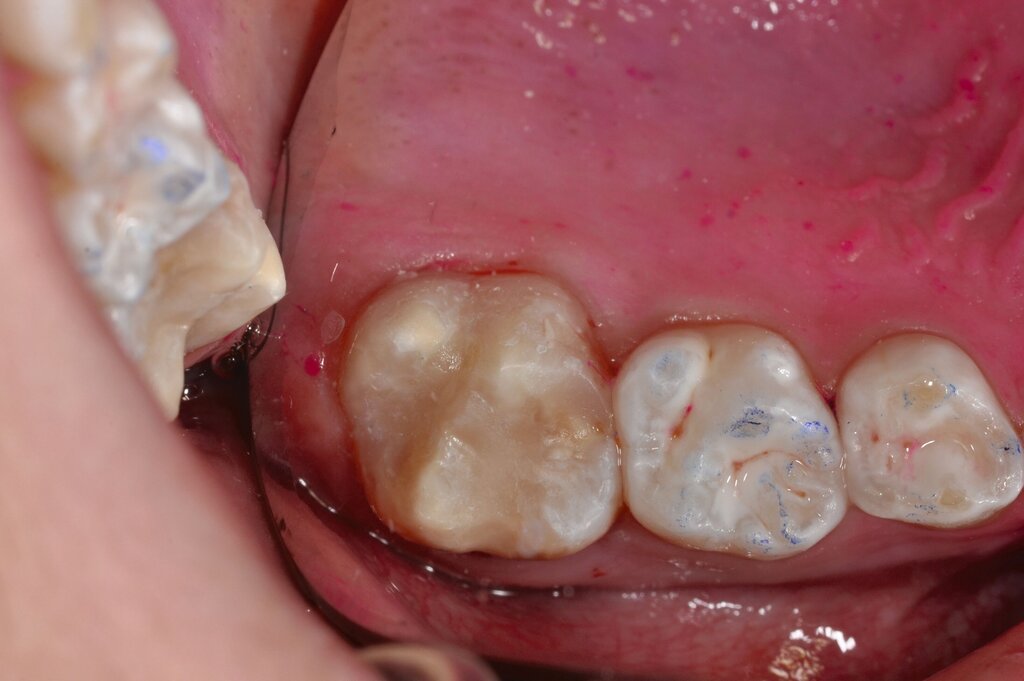

Indirekte Versorgung mit zahnfarbenen Restaurationen

Für größere Defekte an MIH-Molaren müssen häufig tragende Höcker ersetzt werden. Dies stellt eine besondere Herausforderung dar, weil in diesen Fällen große Dentinflächen abgedeckt werden müssen (Abbildung 10). Da die direkte Kompositversorgung eher zur Materialermüdung und zum Verschleiß neigt, schlägt das Würzburger Konzept in diesen Fällen die indirekte adhäsive Versorgung der Zähne vor.

Der vorliegende Fall veranschaulicht den langen gemeinsamen Weg, den die Kinder mit dem Zahnarzt während der Schulzeit gehen. Eine hochqualitative indirekte Versorgung lässt sich bei durchbrechenden Zähnen kaum umsetzen. Außerdem muss bei der Präparation viel Zahnhartsubstanz geopfert werden, so dass bei den jugendlichen Zähnen ein hohes Risiko der Eröffnung der Pulpakammer bestehen würde.